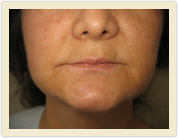

| Before Photo | After Photo |

| Before Photo | After Photo |